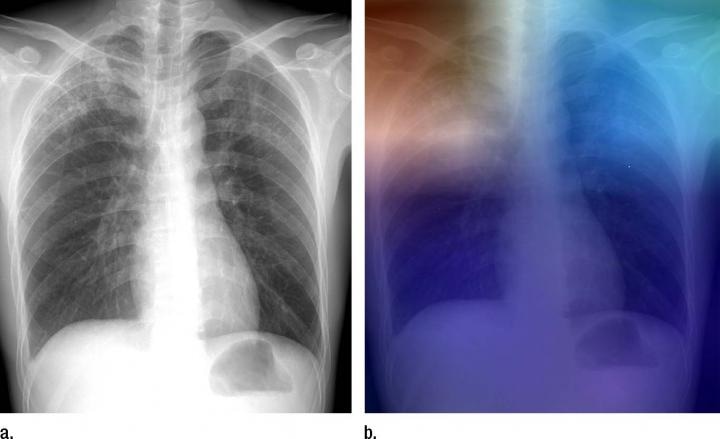

CREDIT: Radiological Society of North America.

To help screening and assessment efforts in TB-rampant areas with inadequate access to radiologists, researchers are starting to train artificial intelligence models to detect tuberculosis (TB) on chest X-rays. The work has been reported online in the journal Radiology.